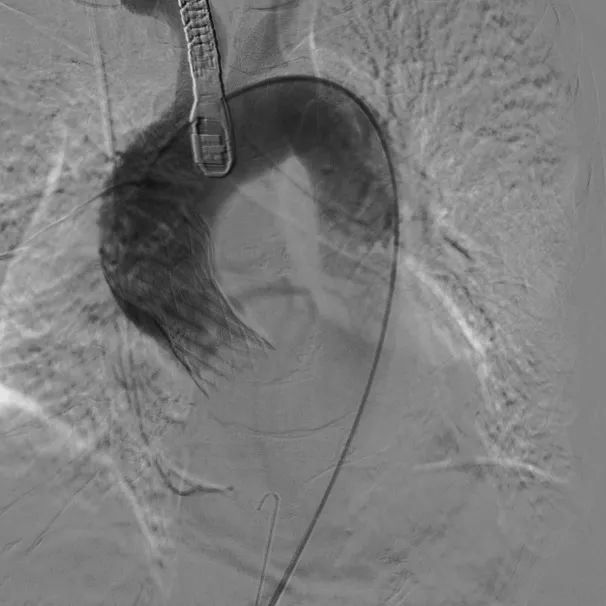

根部造影;直头导丝顺利跨瓣

23mm球囊预扩,冠脉显影正常;输送器顺利过弓

初次释放,无冠窦畸形猪尾难以到达窦底,定位带来挑战;释放至工作位,瓣膜(AV29)位置偏低

瓣膜(AV29)完全回收后重新定位释放

瓣膜(AV29)工作位正交体位造影位置良好,左冠显影正常

瓣膜(AV29)完全脱钩释放后23mm球囊充分后扩,冠脉灌注良好

最后造影